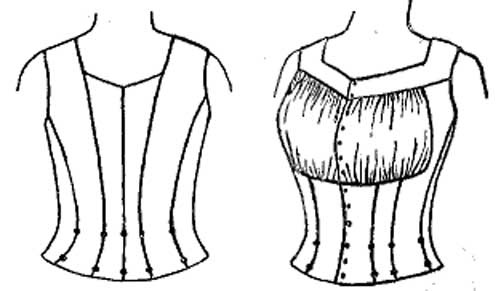

It is a great mistake to clothe children too warmly, indeed, the same may be said of adults. Garments should always be loose and porous, so as to allow of the beneficial action of the air on the skin. One of the objections to corsets is that they do not fulfil these conditions (see Tight Lacing, Skin, Care of.)